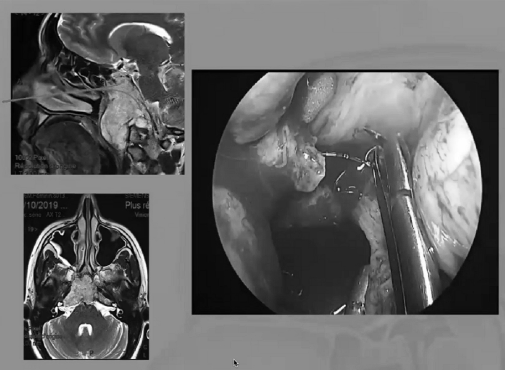

“福教授认为显微镜和内镜技术之于复杂颅底疾病,应是互补(complementary),而不是竞争(competitive)关系,更不是互斥(opposite)关系。这理念也贯彻在他每一例手术中,对于复杂复发的脊索瘤,更多的是显微镜下切除后使用各种角度内镜进行观察,对残余肿瘤的清缴。通过延长和塑形柔软的冲洗管头部,是完成筷子技术的诀窍。”

▼下图所示案例肿瘤看着很大,然后用30度、45度甚至70度的内镜,我们有很多带角度的器械,利用这些器械就可以切除肿瘤。可以先切开黏膜,然后把蝶窦内的黏膜推开,然后进入肿瘤。目前我们正在努力的开发这方面的器械,没有这些器械我们是做不了手术的。

▼下面就是我所说的有角度的器械,最后我们用脂肪来修补,我们在内镜下做缝合,在内镜下做缝合很复杂难度很大,所以很花时间,但是它是值得的。